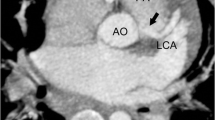

One hundred and twenty-eight-slice CT scanner was accurate in revealing pulmonary artery anomalies. CT pulmonary angiography was superior to echocardiography in the visualization of the morphology of the pulmonary artery (PA) congenital anomaly and its associated findings. The commonest pulmonary artery anomaly was atresia, stenosis then hypoplasia and dilatation in addition to aorto-pulmonary artery collateral arteries (Table 1). These anomalies may be isolated or associated with other congenital heart diseases. All cases of pulmonary abnormalities diagnosed on 128-section CT scanner in our study were correlated with echocardiography (all cases), surgery (26 cases), conventional angiography (preoperative diagnosis) 19 cases and 7 cases underwent therapeutic convolutional angiography. In the current study, MDCT could diagnose all cases of pulmonary arterial anomalies with 96% sensitivity, 100% specificity, 98% accuracy, 100% positive, and 94% negative predictive values (Table 2). The commonest pulmonary artery anomaly was atresia in 16 cases (30%) (Figs. 1, 2, and 3). Pulmonary atresia with a ventricular septal defect in 11 cases, pulmonary artery atresia with intact ventricular system 4 cases, and 1 case complex pulmonary atresia. The most common associated finding is PDA, followed by stenosis of pulmonary artery in 13 cases (25%), 6 cases type I, 4 cases type II, 3 cases type III, and no case in our study found type IV Figure 4 shows type I pulmonary stenosis, then hypoplasia of main pulmonary artery in 10 cases (20%) or its main branches (Fig. 1) and pulmonary artery dilatation in 8 cases (Figs. 5 and 6). Some of the anomalies affect both aorta and pulmonary artery (Figs. 4, 5, and 6). In our study, there was a patent ductus arteriosus (27 cases) (Figs. 1 and 6) and truncus arteriosus (2 cases). In our study, we found aberrant right pulmonary artery (Fig. 5) (3 cases), aberrant left pulmonary artery (Fig. 7) (2 cases), left pulmonary artery sling (1 case), aberrant right subclavian artery (Fig. 6) (4 cases), both aberrant right subclavian artery with left pulmonary artery (Fig. 8) (2 cases). CT can be used for accurate detection of post-treatment complications, in our study we have one case shows fistula between coronary arteries and right ventricle (Fig. 9). CT facilitates the assessment of extracardiac structures as congenital tracheal stenosis (Fig. 8). However, CT angiography was not accurate for detecting valvular diseases of the heart. The intraoperative findings were consistent with the pulmonary CT angiographic findings.

A 5-week-old baby with pulmonary artery aneurysm detected on echocardiography. a Axial CT shows the left pulmonary artery (LPA) arises from ascending aorta (AA) and marked aneurysmal dilatation of the right pulmonary artery (RPAA), left SVC noted (arrow). b The right ventricle (RV) gives off the right pulmonary artery (RPA) which shows aneurysmal dilatation (RPAA). c The four cardiac chambers illustrated along with right middle lobe (RML) collapse. d Airway and lung changes: the left (arrow) and right (arrowhead) main bronchi are compressed by the aberrant LPA and RPAA respectively. Due to RML collapse, there was compensatory hyperinflation of the right upper lobe that crossed the midline and herniated into the left side. e 2D Sagittal reformat image shows the origin of LPA from AA; both structures seen anterior to the RPAA